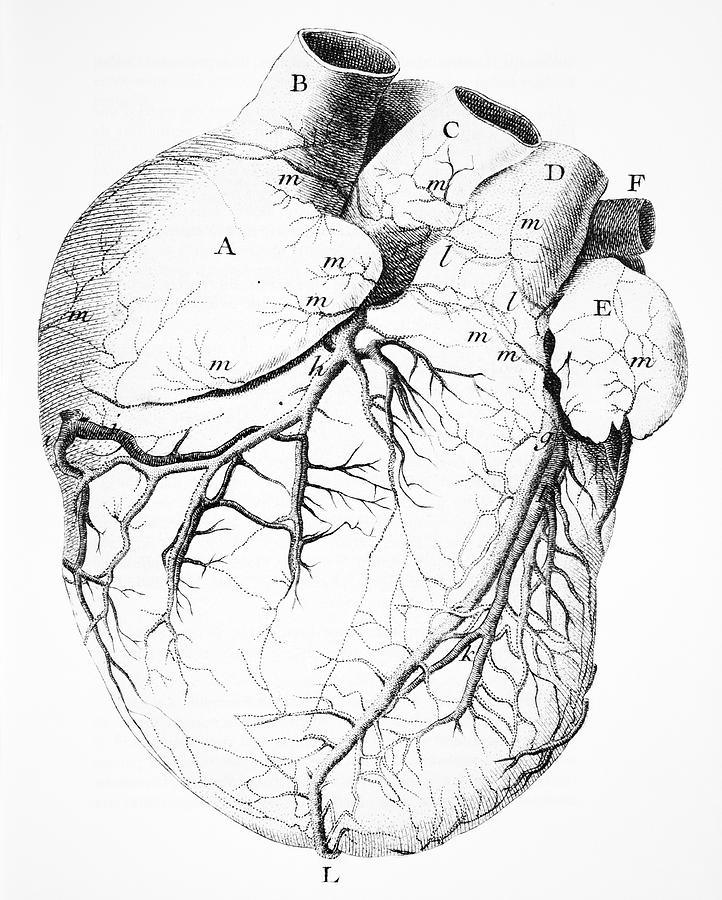

976x976 Vintage Heart Anatomy Illustration Printable 1800s Antique

4098x5352 Anatomical Drawing Bovine Heart Ovam

1079x1300 Drawing A Human Heart Anatomical Human Heart. Engraved Detailed

722x900 Heart Anatomy, 18th Century Photograph By